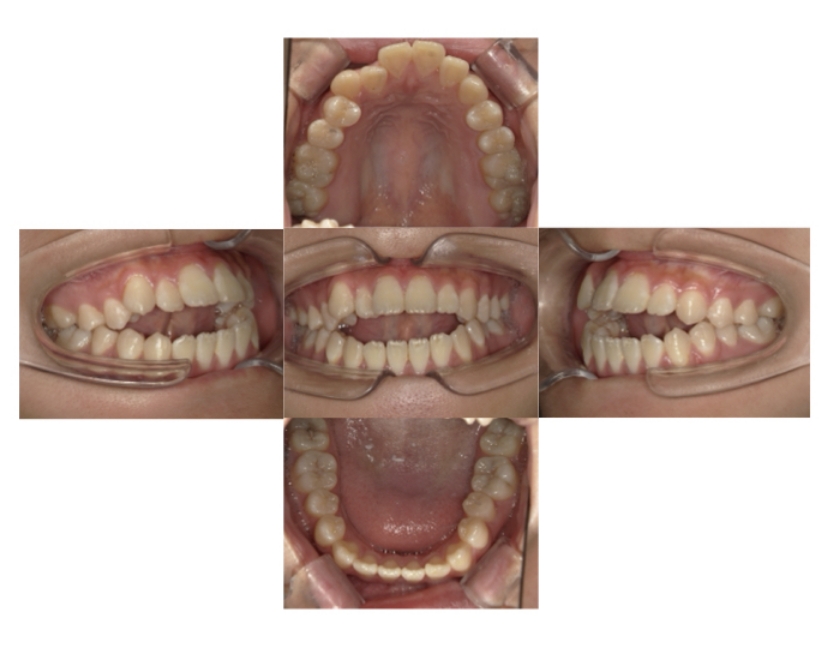

症例3

叢生

抜歯

ブラケット矯正

上下顎叢生(上下の前歯のガタガタ)のケースです。

装置はラビアル(上下表側)で、上下顎の小臼歯を4本抜歯を行っています。抜歯したスペースを使って、上下の前歯の後方移動と叢生(ガタガタ)の改善を行っています。

主訴 八重歯を治したい。

年齢・性別 25歳 女性

お住まいの地域 神奈川県川崎市

治療方針 抜歯スペースを利用して上前歯の叢生(ガタガタ)の改善

抜歯部位 上下顎左右第一小臼歯

使用装置 ラビアル(上下表側)、顎間ゴム

治療期間 1年11か月

治療回数 16回

リテーナー クリアリテーナー

BEFORE

AFTER